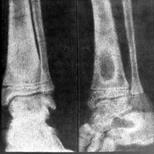

Склерозуючий остео­мієліт Гарре (osteomyelitis scleroticans Garre). При цій формі запалення кістки в ній перева­жають остеосклеротичні процеси з по­ступовим запустінням кістково-мозкового каналу. Захворювання теж пере­бігає торпідно, тривало, з невираженою клінічною картиною: незначний нічний біль у кінцівці, біль під час фізичного навантаження, потовщення кінцівки, локальна болючість під час пальпації. Температура тіла помірно підвищена. Запальний процес ушкод­жує переважно діафізи. Діагноз став­лять на підставі рентгенологічних даних: веретеноподібне потовщення діафі­за кістки, на тлі якого можуть бути помітні невеликі порожнини з дрібни­ми секвестрами. Рідко захворювання починається гостро, з підвищення тем­ператури тіла й інтоксикації. Явища ці швидко минають, і процес набуває хронічного перебігу(рис.7).

Рисунок 7. Рентгенограма склерозуючого остеоміеліту Гарре.

Лікування склерозуючого остеоміє­літу консервативне (антибіотики, фізіотерапевтичні поцедури, електрофорез трипсину).